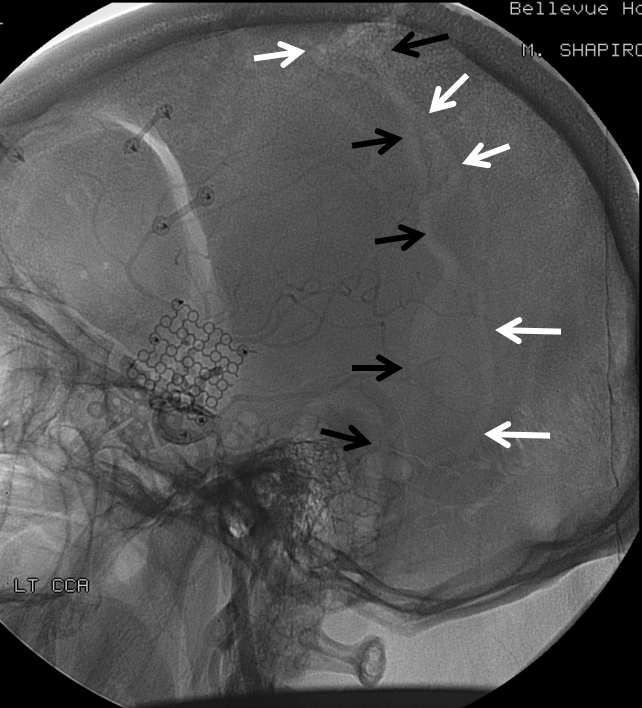

All of the above anatomic knowledge can become very useful in evaluation of venous thrombosis. Numerous collateral pathways develop in this setting attempting to compensate for the loss. The most dramatic cases usually involve the largest channel — the superior sagittal sinus. In this case, a man presented with what initially was thought to be vasculitis-related brain hemorrhage. Subsequent workup led to an angiogram, where sagittal sinus thrombosis with extensive trans-cerebral and trans-osseous emissary vein collateral channels was seen. In retrospect, these findings were present on the patient’s earlier contrast MRI. “Venovibe” or other contrast-enhanced MR venograms can very sensitive, particularly when interpreted with the appropriate index of suspicion. Noncontrast 2-D time of flight MRV I consider to be next to useless as a problem-solving technique. Any thin-slice postcontrast T1 study is vastly superior.